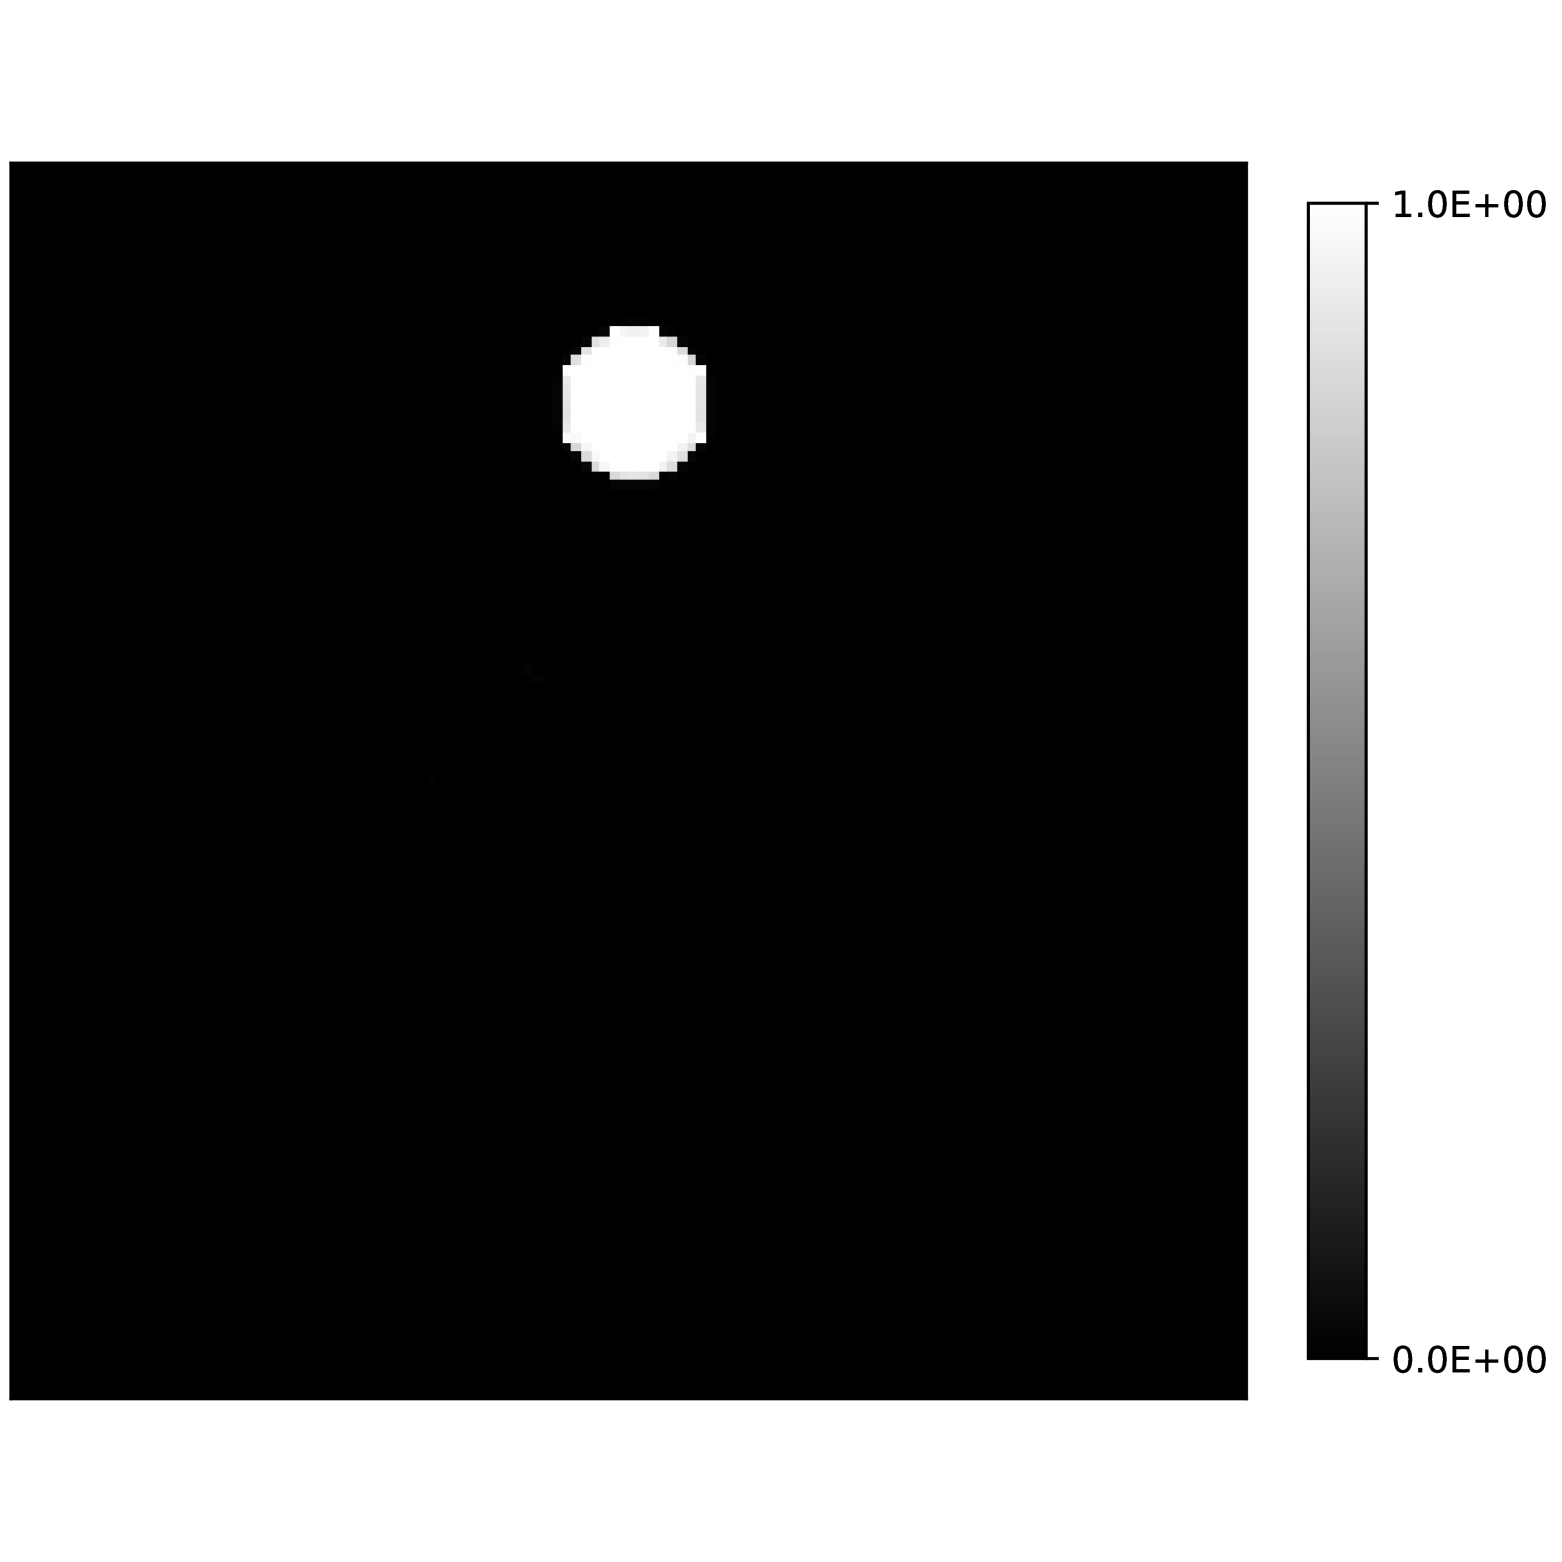

Our theoretical results show that generic concentrations and maps can be recovered exactly even when the fieldmap is not identifiable. To illustrate the impact of this fact, we perform a recovery experiment on a water (Fig. 2(a)), fat (Fig. 2(b)) and silicone (Fig. 2(c)) in silico phantom. The concentrations are all real. The values for the fieldmap and used to generate the signal are shown in Figs. 2(d) and 2(e). The echo times have the form where ms and ms with .

We solve (23) using projected gradient descent as initial iterate a vector with all components equal to one. Forward finite-differences were used to compute the gradient. The bound on the norm of the gradient is Hz at voxels with non-zero signal magnitude, and kHz at voxels with zero signal magnitude. This avoids imposing artificial constraints at voxels with no signal. The step size used is and the termination conditions

In Figs. 2(f), 2(g) and 2(h) show the recovered concentrations of water, fat and silicone, and Fig. 2(j) shows the recovered . These recovered quantities are all qualitatively similar to their true values. In contrast, Fig. 2(i) shows the recovered fieldmap, which differs from its true value. By comparing the errors in the recovered concentrations, we see that they are within a reasonable accuracy except in regions with a large magnitude for the fieldmap gradient, indicating a bound that is too small (Figs. 2(k), 2(l) and 2(m)). A similar behavior is seen in the recovered (Fig. 2(o)). The error for the recovered fieldmap tends to be larger outside the area of the phantom (Fig. 2(n)).